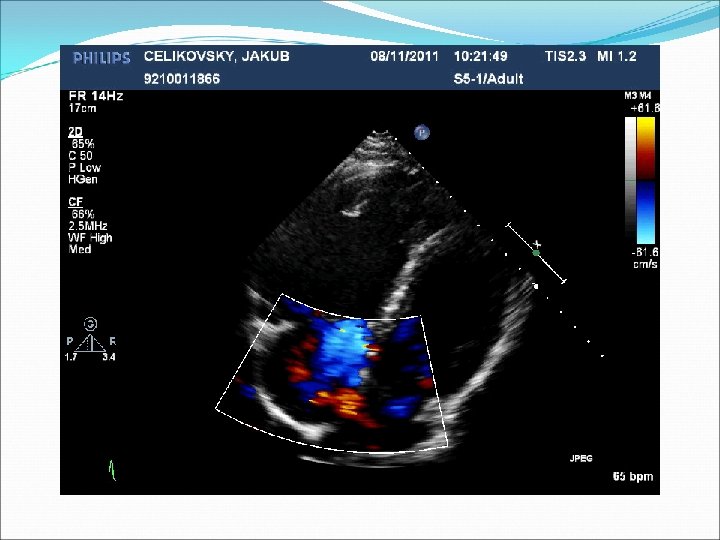

Defekt síňového septa: diagnostika echokardiografie, často jícnová: dilatovaná pravá komora zkratový proud barevným dopplerovským vyšetřením při přítomnosti trikuspidální regurgitace neinvazivně z rychlosti regurgitace odhadovat výši systolického tlaku v plicnici kalkulovat systémový průtok(Qs) ve výtokovém traktu levé komory a plicní průtok(Qp) v kmeni plicnice a počítat jejich poměr EKG: obraz bloku pravého raménka Tawarova u 95 % pacientů je projevem opožděné aktivace dilatované pravé komory Skiagram hrudníku : dilatace pravé komory, pravé síně, dilatace plicnice, zvýšenou plicní kresbu. Katetrizační vyšetření : před uzávěrem defektu u starších pacientů k posouzení plicní vaskulární rezistence a k provedení selektivní koronarografie.